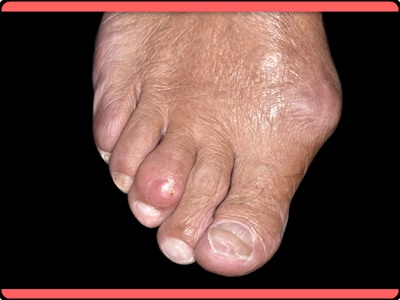

둘째, 손가락 발가락 관절 부위가 부풀어 오르는 증상

통풍은 체내의 요산이 신장을 통해 정상적으로 걸러지지 못하기 때문에 발생합니다. 이는 몸속에 노폐물이나 독소가 필요 이상으로 축척되어 있는 상태라는 것을 말합니다. 때문에 통풍 증상이 시작되면 염증 부위에 심한 통증을 동반할 뿐만아니라 심하게 부풀어 오르게 되며 통증 부위는 빨갛게 붓고 만질 수 없을 정도의 통증을 호소하게 됩니다.